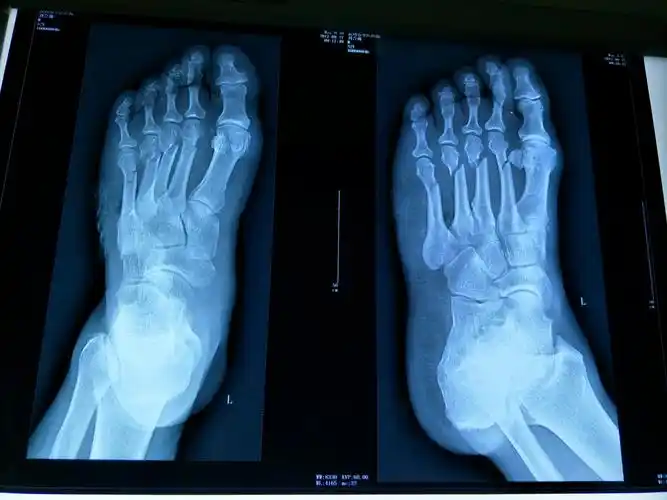

左足第五跖骨基底骨折

脚掌骨骨折 包了石膏一个月 然后又过了40天. 还是不能正常走路.

6岁 女 左足第五跖骨远端骨折

第5跖骨基地部破裂骨折第一天